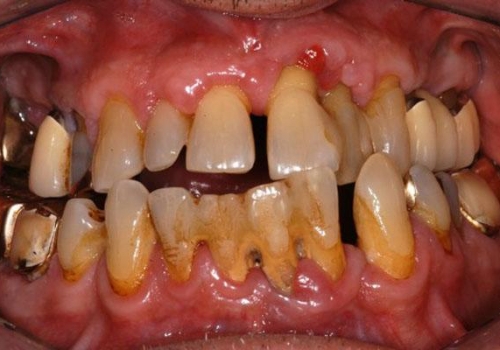

Qeyri-cərrahi parodontoloji müalicədən sonra bəzi hallarda, bu və ya digər bölgədə dərin parodontal ciblər (diş əti və sümük cibi) qalmaqda davam edir. Bu hallarda çox zaman müalicə cərrahi metodların tətbiqi ilə davam etdirilir. Bu zaman əsas məqsəd mövcud parodontal cibin bu və ya digər metodlarda aradan qaldırılmasını təmin etməkdir.

Çünki bu ciblər çox zaman pasiyent tərəfindən yetərincə təmizlənə bilmir. Bu isə həmin bölgəyə tədricən ərp və dolayısı ilə də bakteriya koloniyalarının toplanmasına səbəb olur. Bu proses yenidən yerli iltihabın ortaya çıxmasına səbəb olur. Tətbiq edilən cərrahi metodlar əsasən cibin yerləşdiyi diş bölgəsi, cibin eni, dərinliyi, konfiqurasiyası və s. xüsusiyyətlərə görə müəyyənləşdirilir. Bu zaman məqsəd mümkün olduqda həmin bölgədə bərpa prosedurunu həyata keçirmək, mümkün olmadıqda isə rezektiv müalicənin tətbiqi ilə həmin bölgəyə ərp toplanma ehtimalını azaltmaq və gigiyenik prosedurların icrasını pasiyent üçün rahatlaşdırmaqdır.